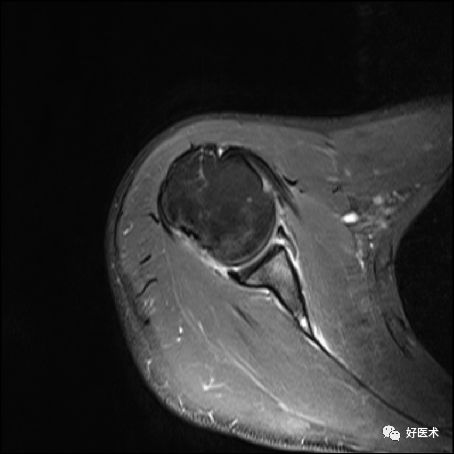

骨性Bankart病变

-

MR间接关节造影1.5T轴位T1W脂肪抑制(TR=460s,TE=90s)